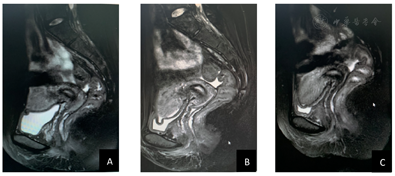

子宫及附件MR平扫+增强(2022年4月2日):宫颈后壁及左侧壁近宫颈外口见团块状等T1、等高T2信号影,DWI序列呈等高信号,边界不清,大小2.9 cm×2.8 cm,病变局限于宫颈,上缘距宫颈内口约3.0 cm,宫旁无受累;盆腔内可见多发小淋巴结影,未见明显肿大淋巴结影。

充分与患者及家属沟通病情后,其坚决要求保留生育功能。经多学科会诊,且与患者反复沟通后,制定了最终的诊疗方案。即先行NACT(紫杉醇+铂类),如化疗有效,再进行保留生育功能手术。充分知情同意后,于2022年4月6日行第一程TP方案化疗(顺铂100 mg/紫杉醇210 mg),化疗后出现Ⅳ度骨髓抑制。遂更改化疗方案。2022年5月2日行第二程TC方案化疗(卡铂500mg/紫杉醇240mg),化疗过程顺利。化疗结束2周后评估病情,肉眼、阴道镜、盆腔MRI均显示肿瘤病灶基本消失(图1,图2)。于2022年6月2日于全身麻醉下行腹腔镜根治性子宫颈切除术+宫颈环扎术,术前行前哨淋巴结显像,双侧未显影,遂行盆腔淋巴结清扫术。术中切除宫颈长度2.8 cm,阴道长度1.8 cm,宫旁组织2 cm,骶韧带长2 cm。探针探查剩余宫颈长约1 cm。切除标本宫颈外口第二象限可见糜烂面,盆腔淋巴结未及肿大。术中冰冻病理:盆腔淋巴结未见明确转移癌;切除的宫颈近内口端:冰冻切面未见明确鳞状细胞癌组织。术后石蜡病理:宫颈:结合免疫组化标记结果,符合基底样鳞状细胞癌。未见明确脉管及神经累及。宫颈切缘:慢性炎症,未见病变组织。阴性切缘1.2 cm。左、右盆淋巴结:均未见转移癌。术后继续TC方案补充化疗3个疗程。